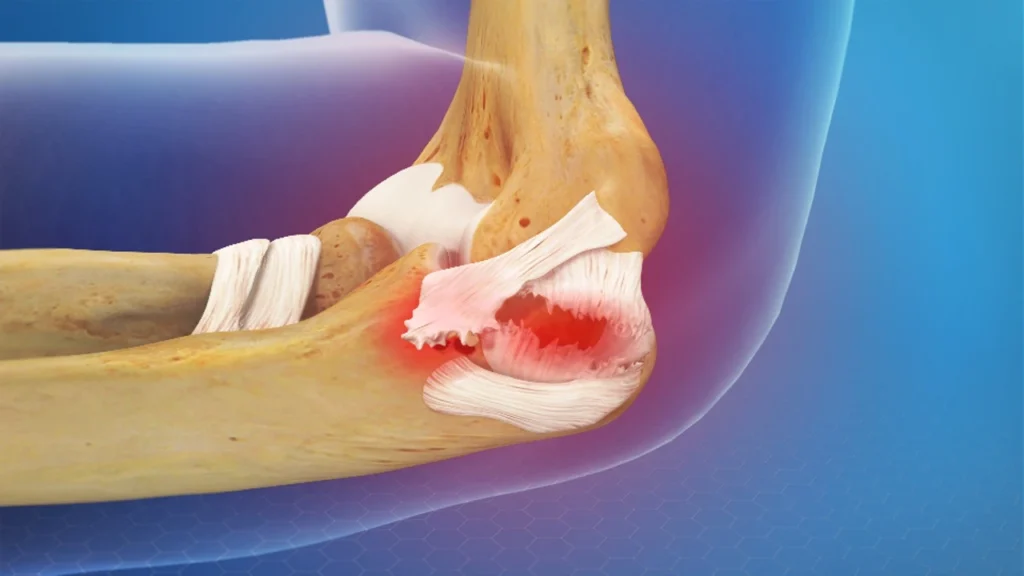

Elbow ligament injuries are common in sports and activities that involve repetitive arm motion, such as throwing or weightlifting. The elbow joint is stabilized by several ligaments, including the ulnar collateral ligament (UCL) and the radial collateral ligament (RCL). Injuries to these ligaments can lead to pain, instability, and limited movement, and are especially common in athletes, particularly those involved in throwing sports.

Acute Trauma: A direct blow to the elbow, sudden hyperextension, or falling onto an outstretched hand can cause an acute ligament tear, especially in contact sports or accidents.

Surgical Repair or Reconstruction: For severe or complete ligament tears, surgery may be necessary. UCL reconstruction (often called Tommy John surgery) is common among athletes and involves replacing the damaged ligament with a tendon graft from another part of the body.